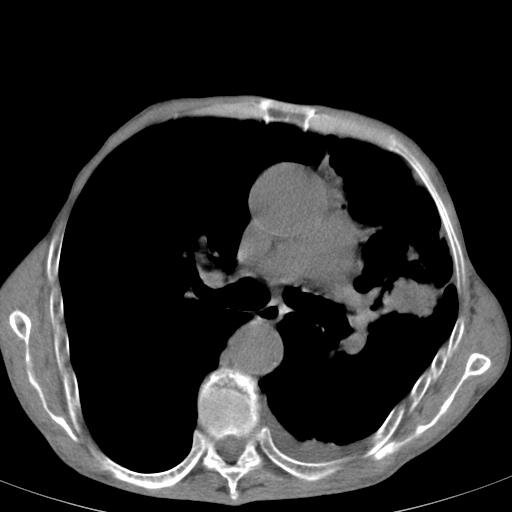

患者78岁,咳嗽胸闷一年余,近月来左侧胸痛;

建议强化,首先考虑左肺癌胸膜转移。

左侧少量胸腔积液,局限胸膜增厚,结合病史,考虑慢性肺炎.

患者左侧胸廓塌陷说明是长期病变,考虑tb性胸膜炎可能性大,另外有明显的肺气肿,建议行结核菌素实验,或者增强扫描

1.慢支肺气肿。2.左肺感染,建议治疗后复查。3.左侧少量胸水。

1.慢支肺气肿。2.左肺感染,建议治疗后复查,待除外继发性肺结核合并感染。3.左侧少量胸水。

1)考虑左肺慢性感染性病变(结核可能)。2)左肺上叶周围型肺癌不排除;建议追踪复查。3)肺气肿。4)左侧胸腔积液,左侧胸膜增厚、粘连。